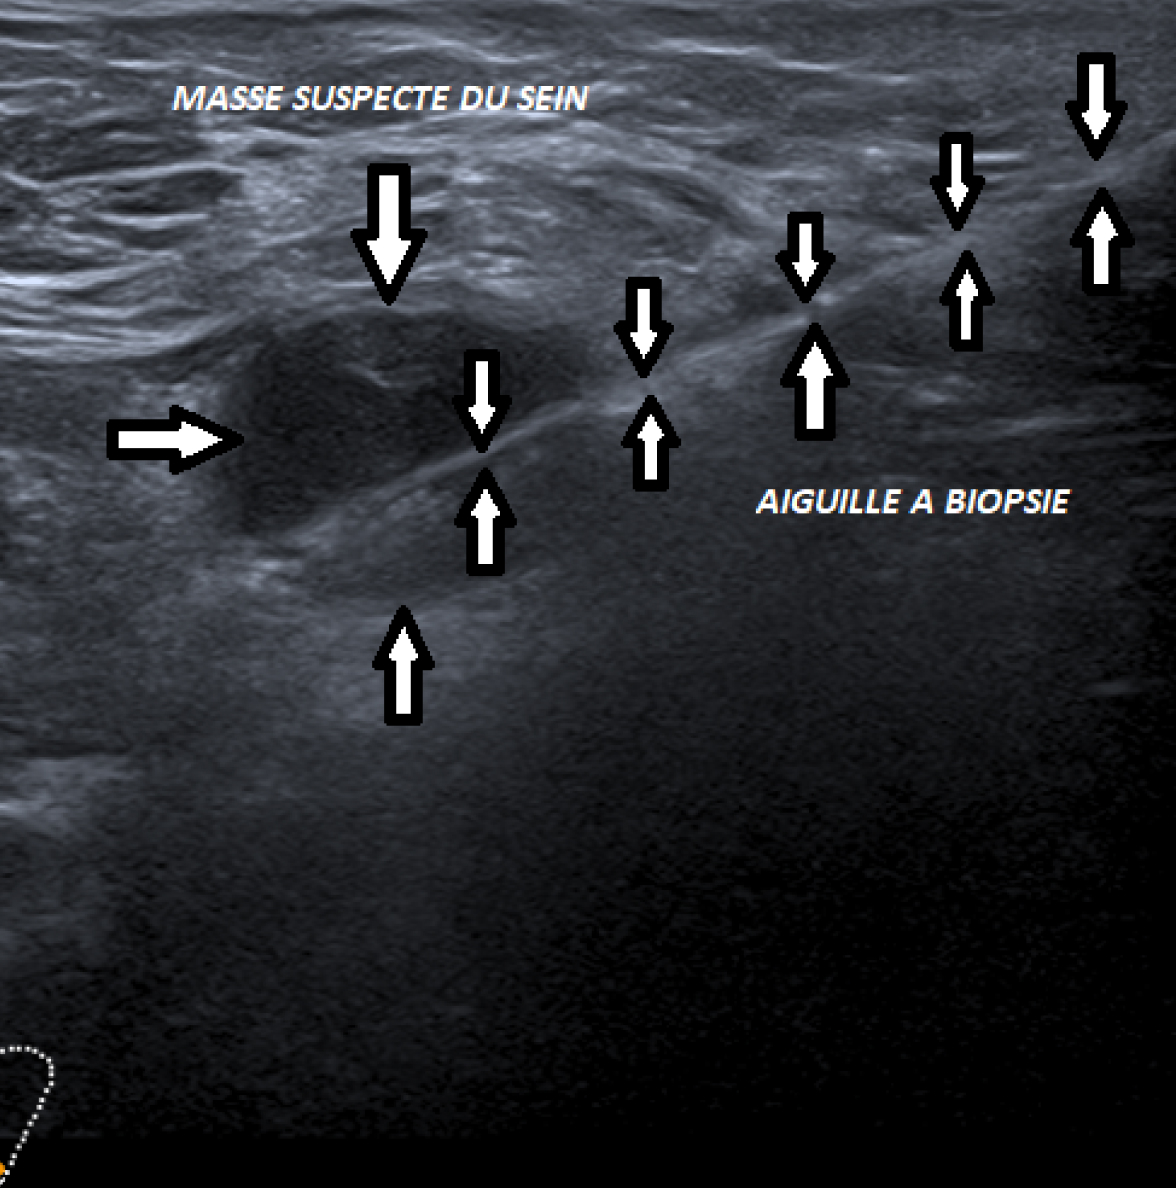

Elle est indiquée surtout pour les masses et nodules bien visibles à l’échographie mammaire.

Une désinfection cutanée ainsi qu’une anesthésie locale constituent des étapes indispensables à toute biopsie mammaire, quel que soit le mode de guidage utilisé. Une microbiopsie mammaire est un geste échoguidé qui se déroule en salle d’échographie et dure environ une vingtaine de minutes.

Lors d’une microbiopsie mammaire réalisée sous guidage échographique, votre radiologue utilise un instrument spécialisé semblable à un pistolet, équipé d’une aiguille de biopsie de 3 à 5 mm de diamètre. En moyenne, 3 prélèvements consécutifs sont effectués, chaque échantillon produisant un léger son de déclic. Un seul point d’insertion cutané sert pour tous ces prélèvements.